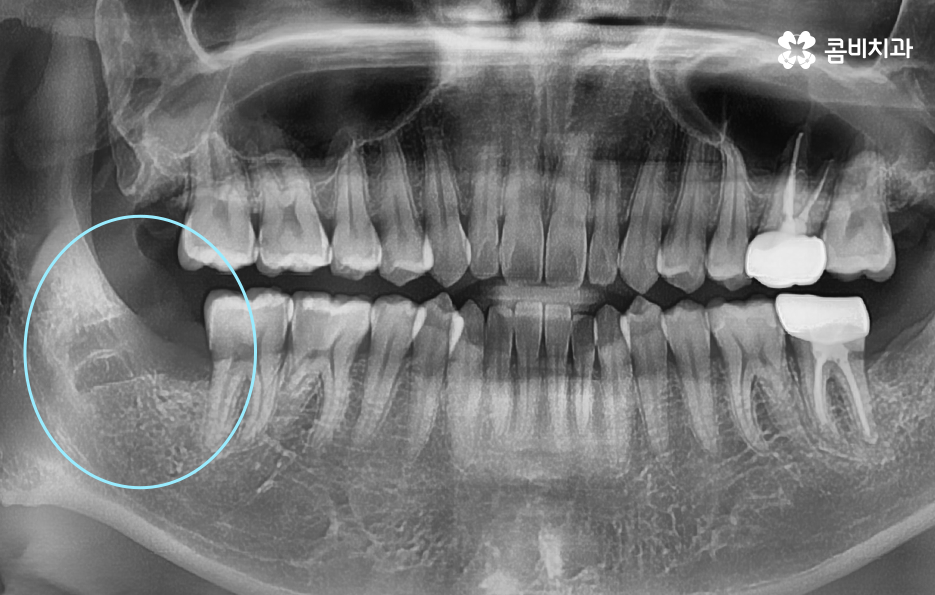

부분매복 사랑니는 겉으로 보이는 부분만으로는 실제 뿌리 모양이나 뿌리의 깊이를 알 수 없으며 X-ray만으로는 앞 어금니와 얼마나 근접해 있는지, 신경과의 거리, 뼈의 형태를 충분히 판단하기 어렵기 때문에 CT 촬영이 권장되는 경우가 많으며 CT는 3D 분석이 가능하기 때문에 사랑니 발치 시 사고 위험을 줄일 수 있고 절개 방향 등을 정확히 계획하는 데 큰 도움이 되고 있었어요

부분매복 사랑니 발치 두 번째 문제는 옆 어금니의 충치와 뼈 손상으로 부분매복 사랑니가 비스듬하게 누운 형태로 자라는 경우가 많은데, 이때 사랑니가 바로 앞 어금니 2번 치아(제2대구치)의 뿌리를 밀어내거나 치아 사이에 음식물이 지속적으로 끼게 될 수 있었어요

이 사이에 끼는 음식물은 아무리 칫솔질을 해도 제거가 어렵기 때문에 앞 어금니가 충치에 취약해지며 실제로 사랑니 때문에 앞 어금니가 충치가 생기고, 결국 큰 신경치료까지 가는 사례가 많은데 더 심하면 앞 어금니 뿌리 주변 뼈가 녹아 앞 치아까지 흔들리는 상태가 되기도 해서 사랑니 자체보다 옆 치아가 더 큰 피해를 보는 경우가 많다는 점이 부분매복 사랑니의 큰 문제점이라 할 수 있어요